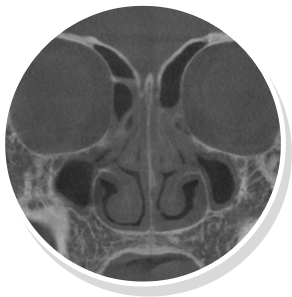

코재수술 CT 전후사진

비염

비중격만곡증

축농증